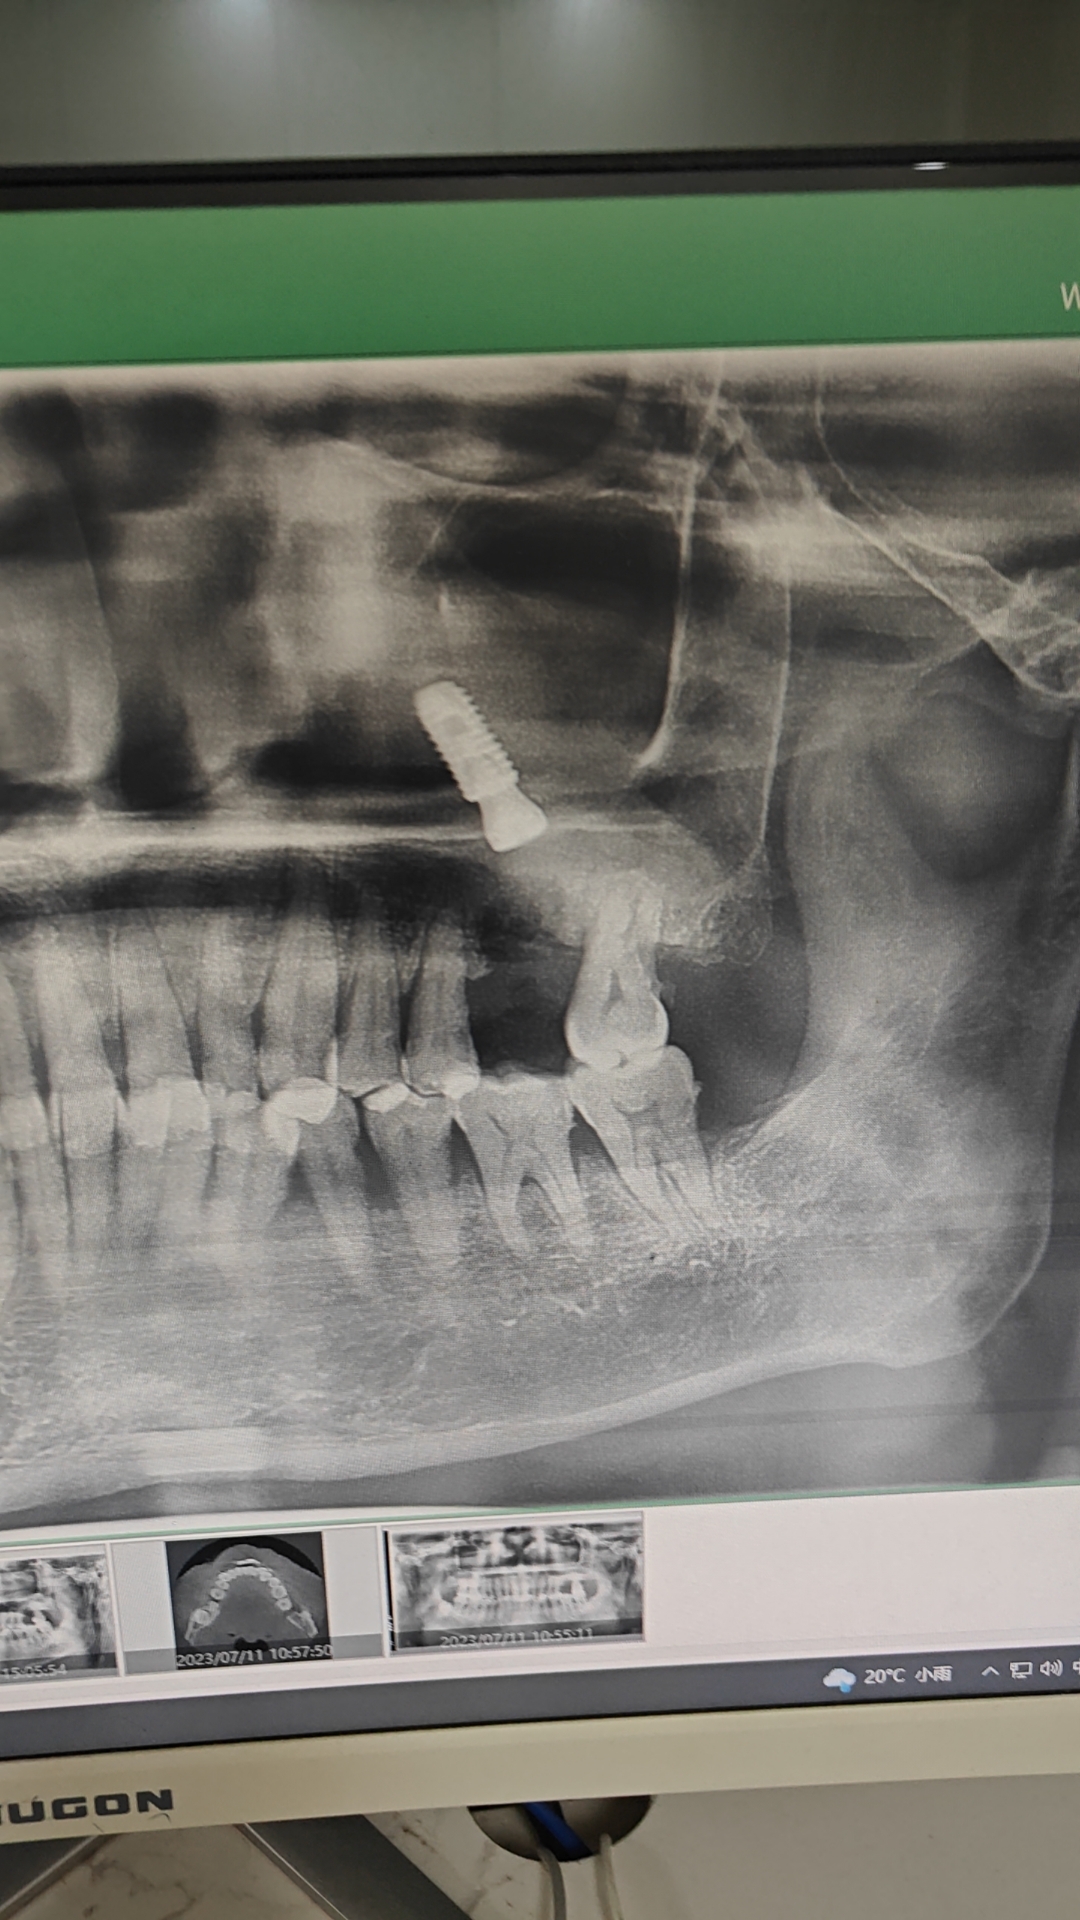

种植牙并发症之一,植体掉入上颌窦

上颌后牙区种植并发症

种植体掉入上颌窦了